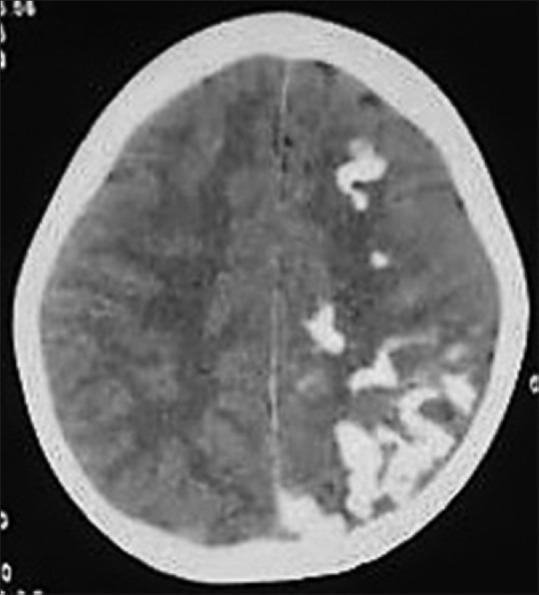

phakomatoses:图文综述。

Phakomatoses: A pictorial review.

Phakomatoses or Neurocutaneous syndromes are a heterogeneous group of disorders and have variable inheritance pattern. Currently, more than 30 entities are included in this group. These disorders primarily affect the central nervous system; however, skin, viscera, and other connective tissues can also be involved with variable clinical presentation. We will describe and illustrate the various radiological findings of the common entities through the iconography of the cases presented to our department.

摘要

phakomatoses或神经皮肤综合征是一组异质性疾病,具有可变的遗传模式。目前,该组包括30多种疾病。这些疾病主要影响中枢神经系统;然而,皮肤、内脏和其他结缔组织也可能受累,临床表现各异。我们将通过提交至我科病例的影像学表现来描述和说明常见疾病的各种放射学表现。